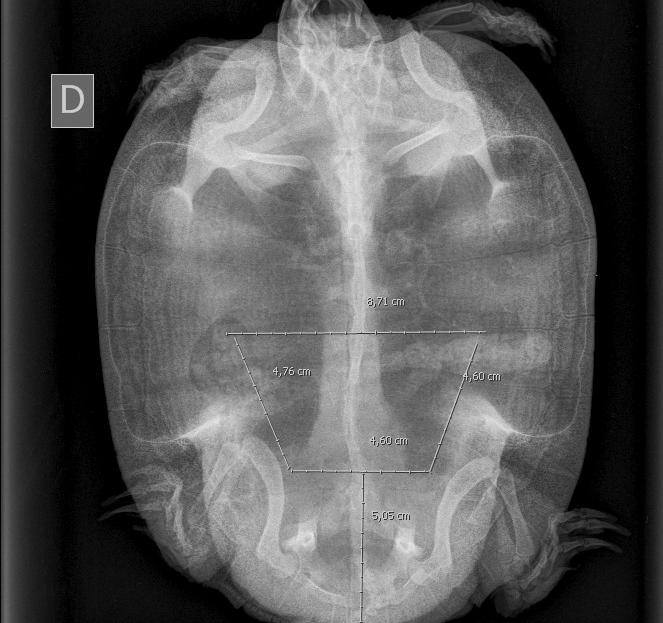

Dada la gravedad de la lesión se propone la realización de una celiotomía exploratoria. Para la planificación quirúrgica se obtiene una radiografía en la que no se detectan signos de obstrucción digestiva, distocia, ni otras anormalidades. Sobre la imagen radiológica se simula una ventana lo más caudal y amplia posible

Figura 3. Simulación de la osteotomía sobre imagen radiológica.